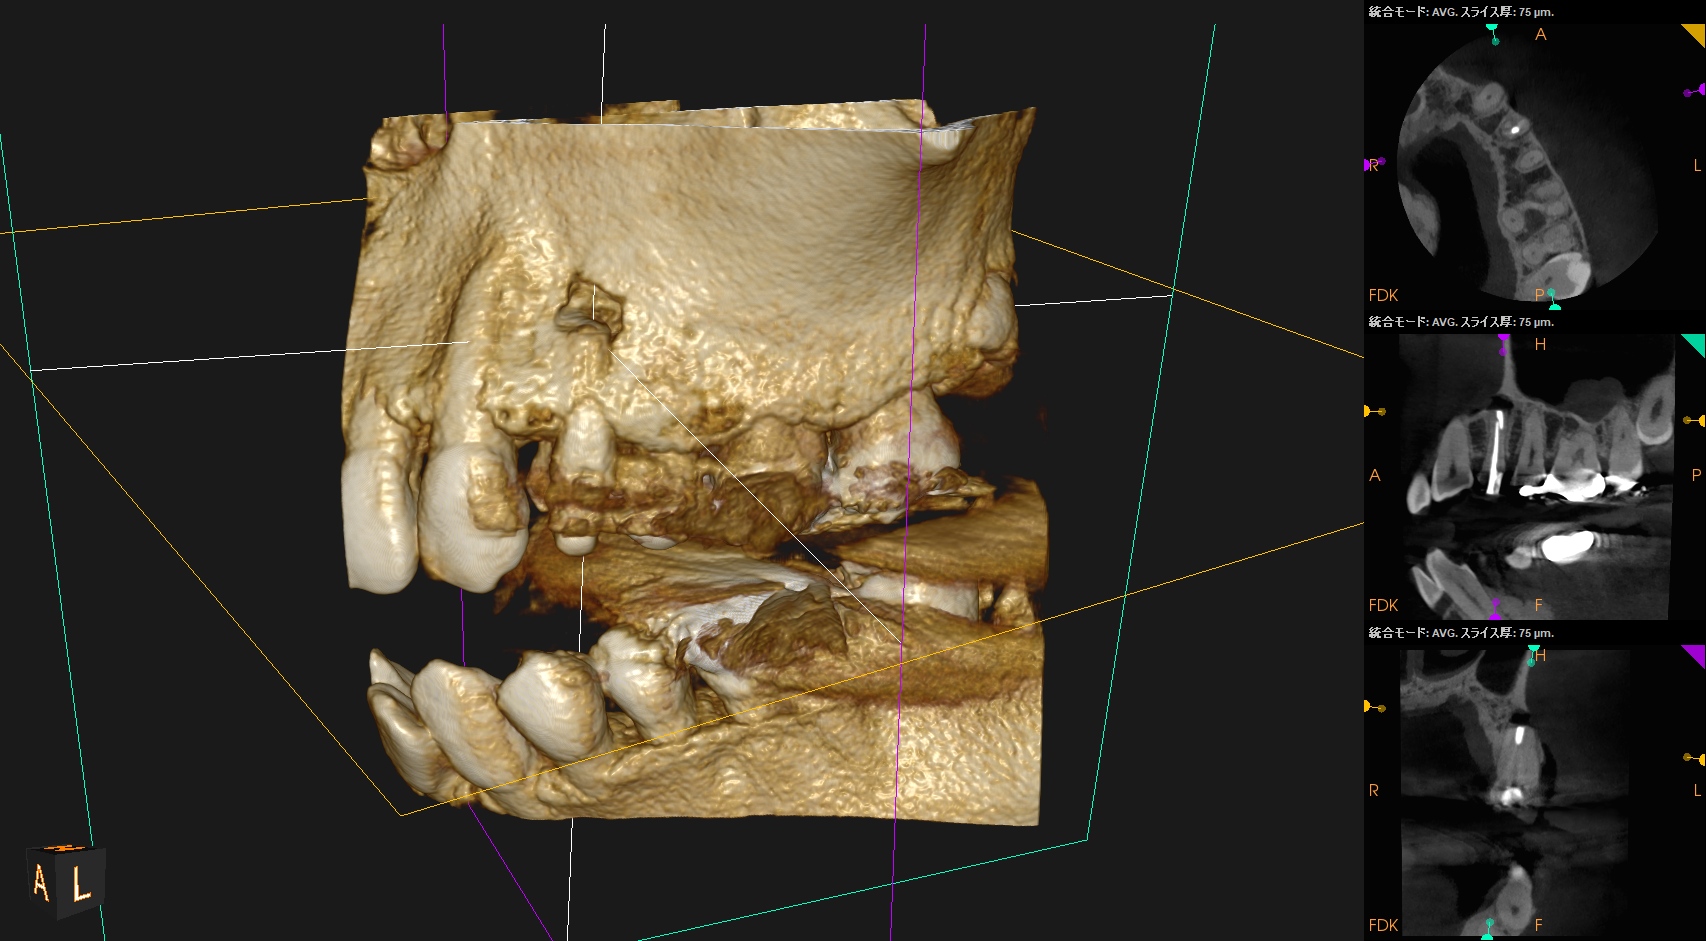

以下のようなケースでも可能なのだろうか?

私(当時Resident)も、

その後の二人のEndodontist(“自称”ではなく、“米国歯内療法学会”が認定する“Endodontist”である)も穿通させられなかったのだ。

何が言いたいか?と言えば、

全ての根管が穿通するとは限らない

ということである。

例えPAやCBCTで根管が見えていても、だ。

CBCTを分析すれば、だ。